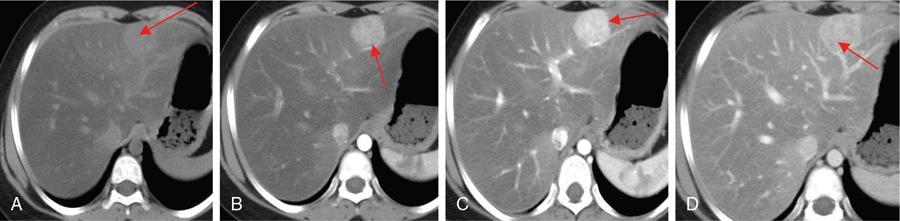

CT

MR